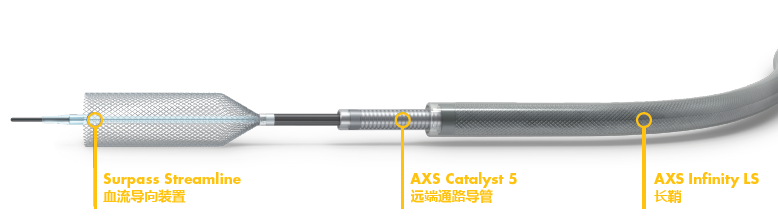

目前国内应用的血流导向装置主要两个:进口的Pipeline(PED)和国产的Tubridge。Surpass的二代产品Streamline是刚刚引进国内的一款血流导向装置,设计上具有多的编织网丝,3mm/4mm支架72网丝,5mm支架96网丝,是一款导流作用更加卓越的血流导向装置。

为了能够更容易的将Streamline输送到位,推荐首先将Catalyst 5送过病变到大脑中,然后通过中间导管输送支架系统。相比用导丝把支架系统带上去,这样的“中间导管远端到位技术”使得手术变得更加简单和安全。当然啦,对于一些平直顺畅的血管,使用导丝输送支架系统也是可以完成手术的。

路图下,Catalyst5在Synchro 微导丝、XT-27微导管的导引下送到大脑中动脉M1远端。

通过Catalyst 5,将Streamline在Synchro 14导引下到达大脑中内。

手术的开始阶段,如我们设想的一样:Neuromax到达右侧颈内动脉,然后将Catalyst 5通过导引到达大脑中M1末端(Catalyst跟踪性好,难度不大),进而顺利将Streamline送到大脑中。

支架打开和贴壁的性能真的很棒,虽然释放过程颇多波折,但是支架释放后完全开放,没有过多的操作去帮助支架打开。虽然还是应用了Cat5和导丝按摩,感觉没起多大作用。支架整套输送系统较硬,如果Cat5无法到位,对于迂曲的血管支架输送可能存在一定的挑战,这是术前就预料到的。一个新的体会就是过于迂曲的血管支架释放也存在挑战,需要充分了解支架系统的设计,正确的释放张力,达到良好的释放效果。